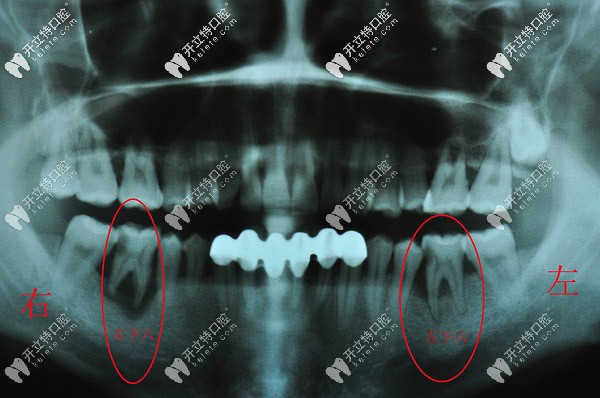

分享一則三度松動牙齒拔除的病例,都是重度牙周炎惹的禍

拔牙牙周炎怎么治療大牙松動發(fā)布時間: 2025-04-13

淄博高新博凡口腔日前接診了一位因重度牙周炎導致的三度牙齒松動拔除病例,關(guān)于三度松動牙是否有保留的必要本文也詳細講解,希望對大伙兒有所幫助!